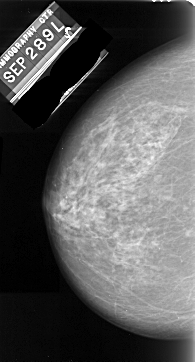

A_1065_1.LEFT_CC

LEFT_CC LINES 5416 PIXELS_PER_LINE 2911 BITS_PER_PIXEL 16 RESOLUTION 42 NON_OVERLAY